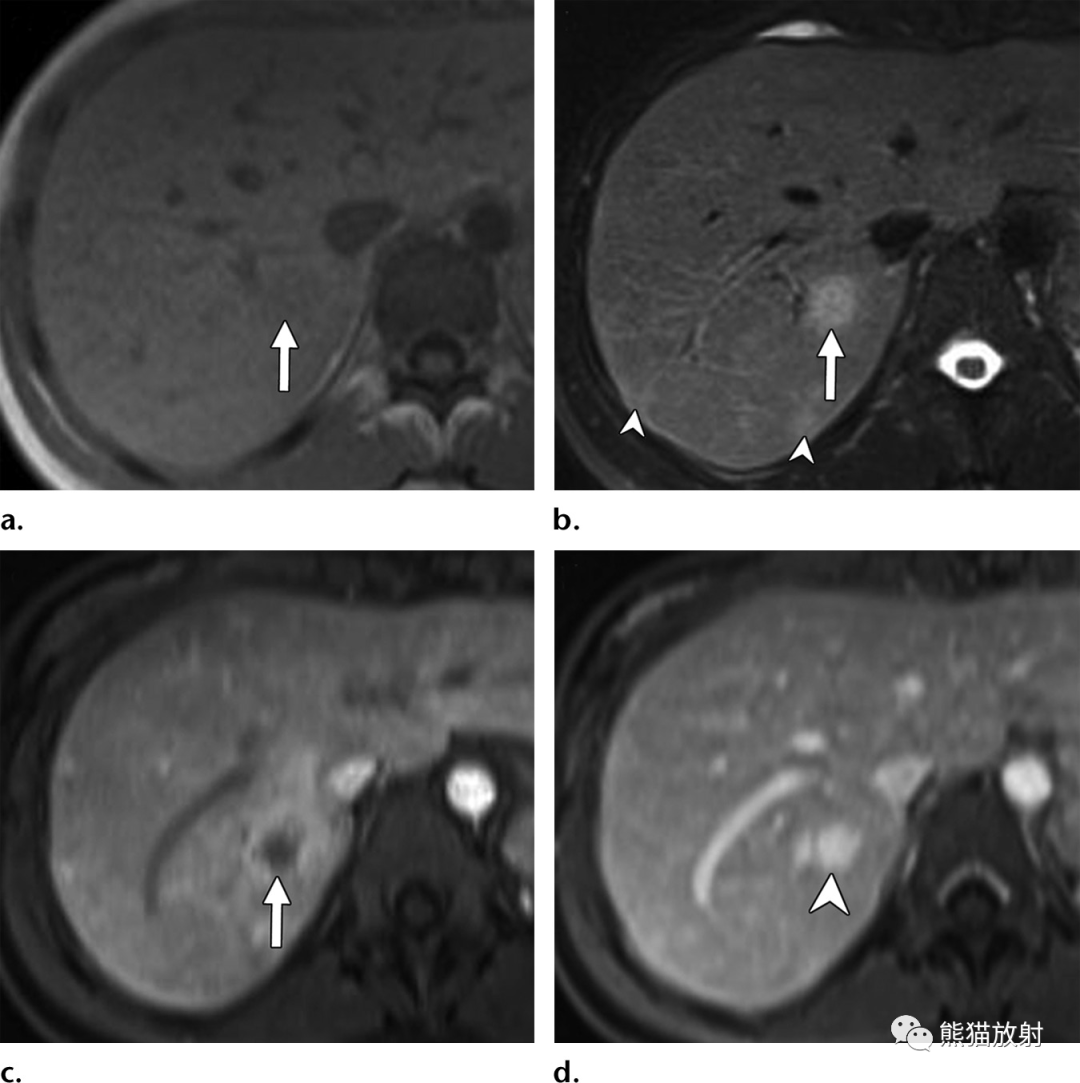

(a)T1WI同相位图像显示肝右叶后段边界不清的等至轻度低信号结节(箭)。(b)脂肪饱和T2WI显示结节呈中高信号(箭),后方肝被膜下见数个较小结节(箭头)。(c)增强动脉早期图像显示结节周围不规则明显强化。(d)增强延迟期结节内部延迟强化,由于造影剂滞留在病灶内扩张的肝窦内,因此达到与周围肝静脉结构相似的信号强度。